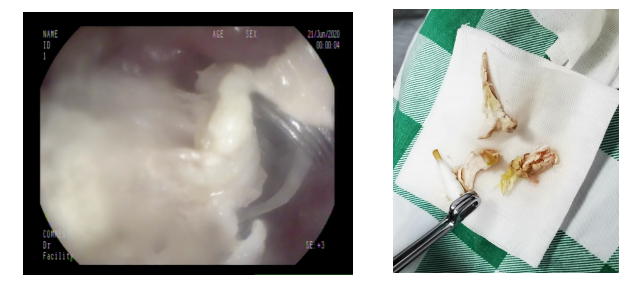

在消化内科梁政主治医师、麻醉科许永健主治医师、何少玲主管护师、以及马宗宝护师的合作下,鸡肉残渣及鸡骨被小心翼翼地顺利完整取出,经胃镜检查,未发现有新的粘膜受损。